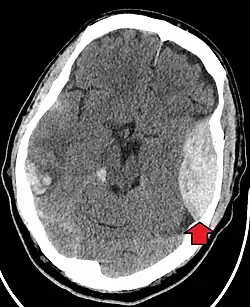

Trauma craniano contuso

A principal preocupação clínica com o trauma contuso na cabeça é o dano ao cérebro, embora outras estruturas, como crânio, face, órbitas e pescoço, também possam estar em risco.[9] Após haver avaliação das vias aéreas, circulação e respiração, um colar cervical pode ser colocado no paciente se houver suspeita de trauma no pescoço. Em seguida, procede-se com levantamento secundário de evidências de que haja trauma craniano, como a presença de hematomas, contusões, lacerações e escoriações. Além de se observarem lesões externas, o exame neurológico completo é tipicamente realizado para que sejam avaliados danos ao cérebro. Dependendo do mecanismo da lesão e das avaliações, tomografia computadorizada do crânio e do cérebro pode ser realizada. Ela normalmente é feita para avaliar se há hemorragia intracraniano ou fratura dos ossos cranianos.[18]

O traumatismo cranioencefálico (TCE) é uma causa significativa de morbidade e mortalidade, sendo mais comumente causada por quedas, acidentes automobilísticos, lesões esportivas, acidentes de trabalho e agressões. É a causa mais comum de morte em pacientes de até 25 anos. O TCE é classificado de leve a grave, com maior gravidade sendo correlacionada com aumentos da morbidade e mortalidade.[18][19]

A maioria dos pacientes com grave traumatismo cranioencefálico apresenta uma combinação de lesões intracranianas, podendo ser incluídas lesão axonal difusa, contusões cerebrais e hemorragias intracranianas, como hemorragia subaracnóidea, hematoma subdural, hematoma epidural e hemorragia intraparenquimatosa.[9][18] A recuperação da função cerebral após uma lesão traumática é altamente variável e depende das lesões intracranianas específicas existentes. Porém, existe uma significativa correlação entre gravidade da lesão inicial e nível de função neurológica durante a primeira avaliação e o nível de déficits neurológicos duradouros.[18] O tratamento inicial pode ser direcionado à redução da pressão intracraniana se houver preocupação com inchaço ou sangramento dentro do crânio, podendo exigir cirurgias como a hemicraniectomia, na qual parte do crânio é removida.[9][18]